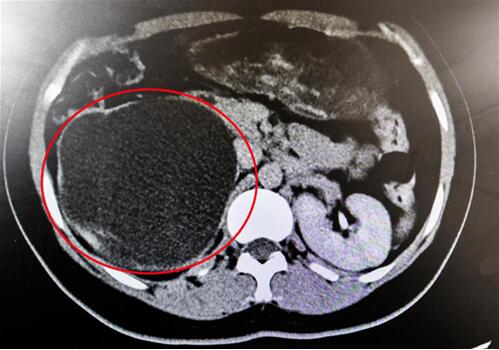

紅圈部分為手術(shù)后腎臟輪廓逐漸清晰。院方供圖

手術(shù)原理并不復(fù)雜,找到并切掉閉鎖的輸尿管,再將健康的輸尿管重新接起來即可,但看似簡單,做起來卻并不容易。首先使用輸尿管鏡給患者檢查,醫(yī)生發(fā)現(xiàn)輸尿管鏡前進(jìn)10cm左右無法繼續(xù)上行,此處的輸尿管已經(jīng)完全閉鎖了。于是醫(yī)生在患者右下腹部切開一個(gè)5公分的切口,逐層揭開進(jìn)入腹膜后間隙,開始尋找閉鎖的輸尿管。

終于,功夫不負(fù)有心人,他們在粘連嚴(yán)重的腹膜外組織中找到了輸尿管!當(dāng)時(shí),靳文生主任心里緊繃的一根弦終于松了下來,接下來的手術(shù)過程也變得順暢了。